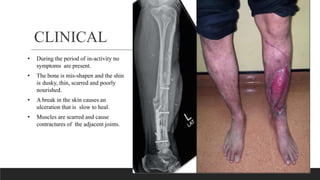

CLINICAL

• During the period of in-activity no

symptoms are present.

• The bone is mis-shapen and the shin

is dusky, thin, scarred and poorly

nourished.

• A break in the skin causes an

ulceration that is slow to heal.

• Muscles are scarred and cause

contractures of the adjacent joints.